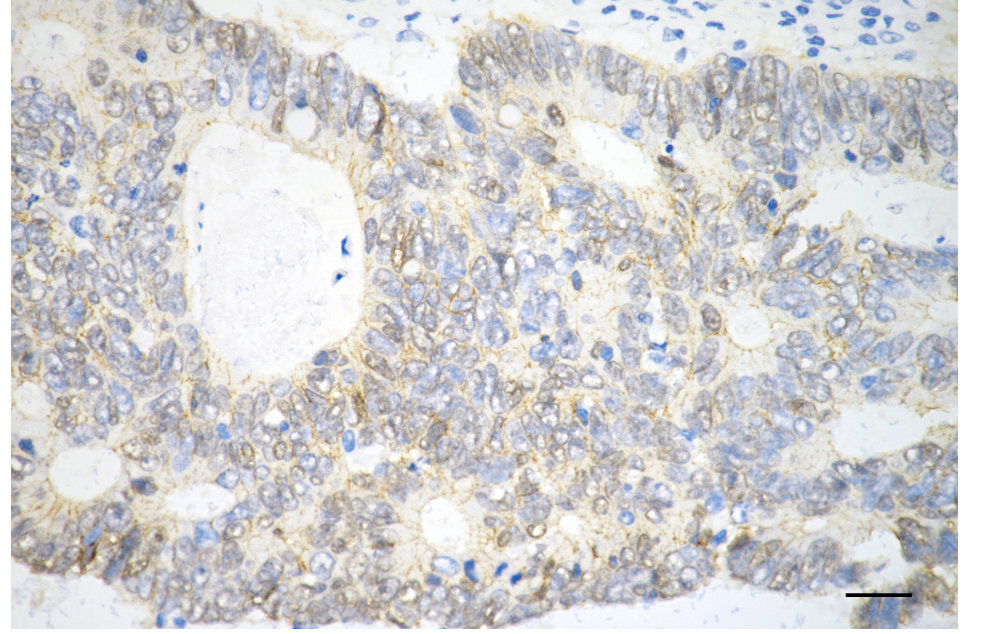

• Immunohistochemistry was performed on paraffin-embedded human sigmoid colon carcinoma using beta catenin antibody. Antigen retrieval was done in sodium citrate buffer (pH 6.0). DAB was used for detection, with hematoxylin counterstaining. Images were acquired using a Nikon Ci-L Plus microscope (40× objective). Scale bar: 25 μm.